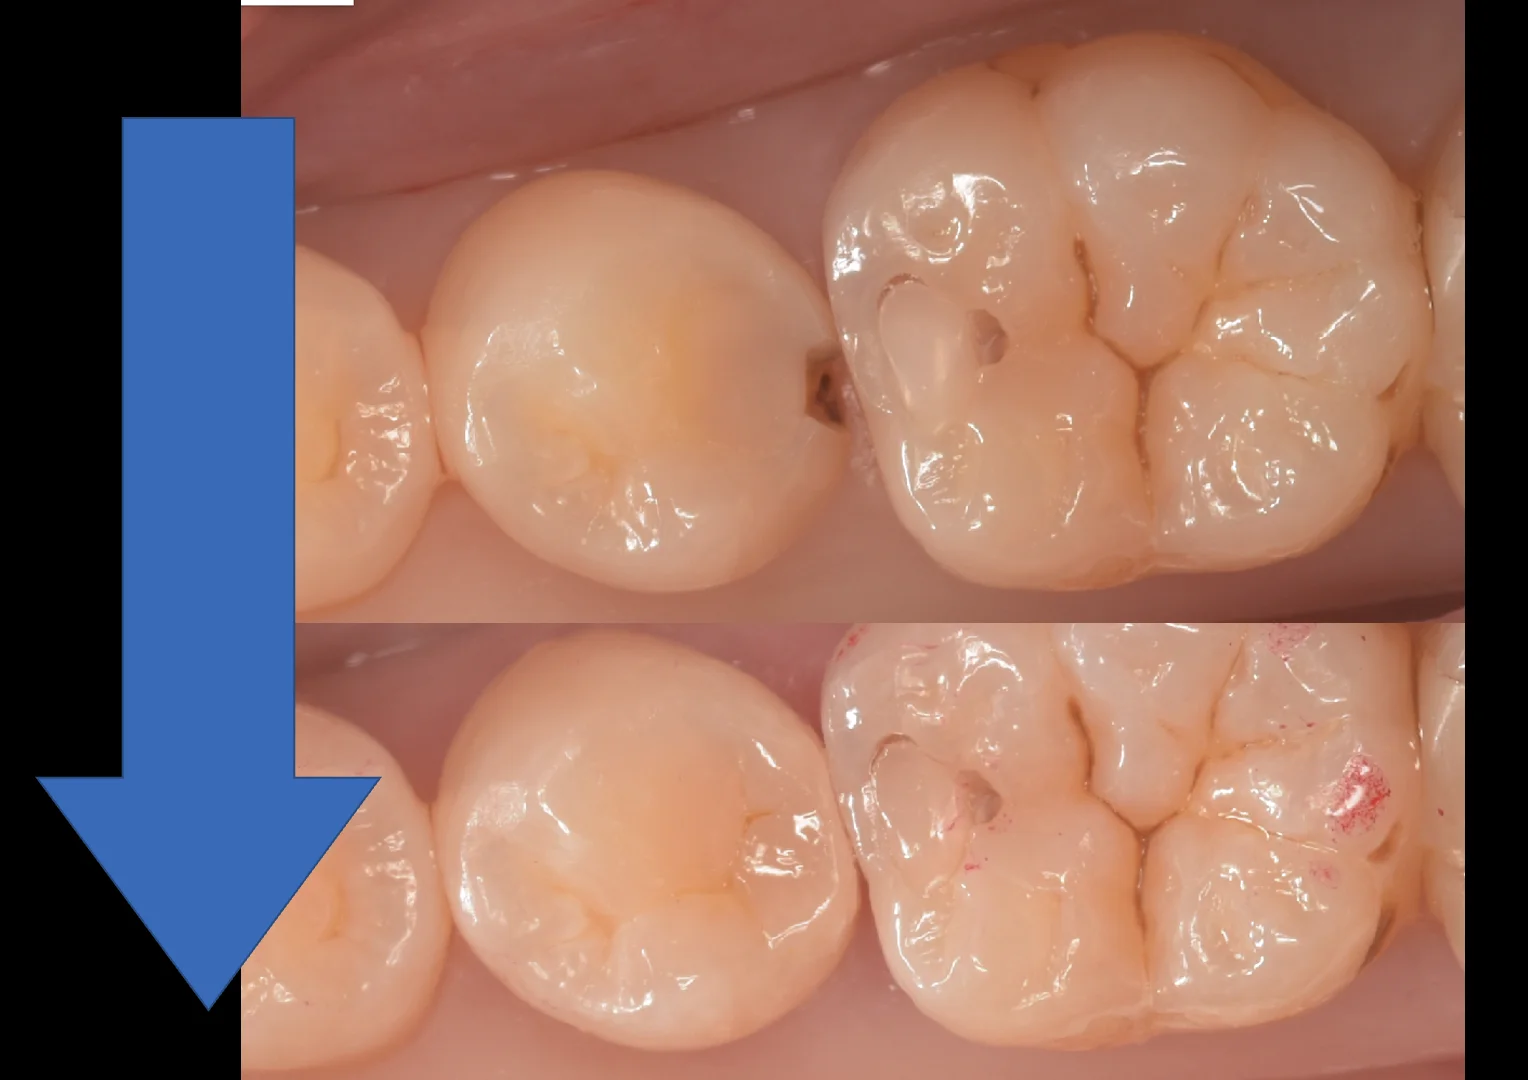

そしていつものやり方で詰め終わったのがこちらになります。

歯の溝の色は手前の歯で薄く、奥で濃くなっているタイプの方でしたので、そうなるようにやや色を調整して入れています。

噛み合わせの調整もほぼ不要だったためそのまま研磨して終了です。

術前術後の写真がこちらになります。